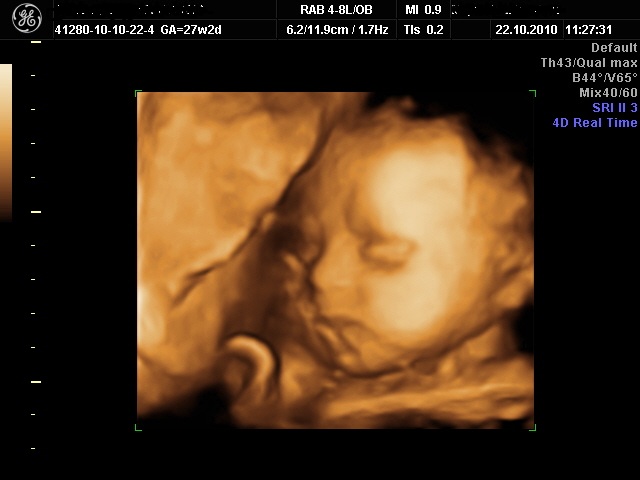

cypress Skrevet 22. oktober 2010 Forfatter #1464 Skrevet 22. oktober 2010 Nå har jeg vært på UL! Det var fantastisk gøy!!! Lille bolla lå i seteleie med beina nøyaktig der jeg trodde , og det første vi så var at hun tok en megagjesp! Jeg visste ikke at de gjespet i magen!! Jeg trodde gjesping var for å få i seg ekstra oksygen, og det makes no sense i magen, for der puster hun jo ikke! Men men, det var gøy å se i hvert fall. Ellers var alt på plass, 10 fingre og 10 tær, 4 hjertekammere og jentetiss! 100 % sikkert sa damen! Hun brente til og med et bilde av underlivet hennes til oss, så vi kunne ha som dokumentasjon. Jeg skjønte ikke så mye av akkurat det bildet, men... Jeg tror på at det er en jente nå! Ellers hadde hun hendene en del foran ansiktet, men vi fikk noen fine bilder uten hender også. Og et par bilder av søte små føtter. :rødme: Jeg prøver å legge ved et lite bilde, håper jeg fikk det til..

cypress Skrevet 22. oktober 2010 Forfatter #1465 Skrevet 22. oktober 2010 Og hun ligger forresten midt på streken for normalen når det gjelder størrelse. Hun er visst ca 33 cm og rett over 1000 gram. :rødme:

cypress Skrevet 22. oktober 2010 Forfatter #1474 Skrevet 22. oktober 2010 Ja, kanskje det er pustetrening?? :klø: Hmm.. rare greier.. Jeg blir aldri lei av å se på bildet jeg!!! Nå har jeg det som bakgrunnsbilde på dataen på jobben også! Den litt "krøllete" dingsen som går skrått over haken og det ene kinnet er forresten navlestrengen, men det skjønte dere kanskje. Lurer litt i bakhodet på navn om dagen... Har et par forslag som liksom ikke slipper taket. Mannen er ikke avvisende til noen av dem heller, så kanskje vi slipper å lete videre. Må bare bestemme oss for hvilket som er best...